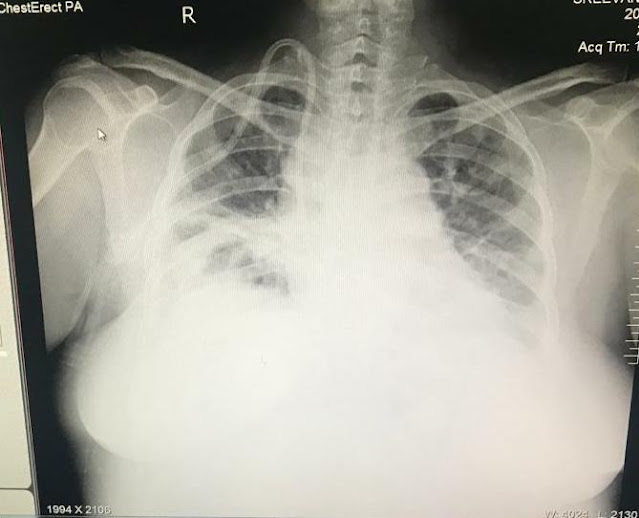

1 month back she presented to our hospital dyspneic with bilateral pedal edema extending to her thighs, her Serum creatinine was 9 mg/dl at this point and she was taken up for hemodialysis.

She is obese and appeared to be pale.

Lungs - Bilateral inspiratory crackles in all the lung fields

She has been having temperature spikes since the past 20 days and has also been giving a history of dry cough since 3 months.

The past 3 days she has been complaining of productive cough with scanty, mucoid sputum.

Her Serial Chest X rays

15/7/2020

17/7/2020

18/7/2020

20//7/2020

Her HRCT CHEST shows

Right lower lobe consolidation

Bilateral lung cavities